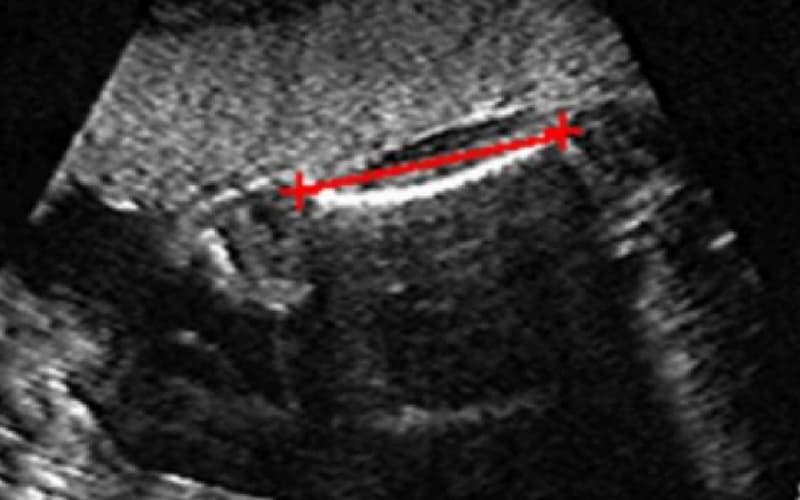

Trong hành trình mang thai, việc theo dõi các chỉ số sinh học qua siêu âm là cách cần thiết để đảm bảo bé yêu đang phát triển khỏe mạnh. Trong đó, chiều dài xương đùi thai nhi (FL – Femur Length) là một trong những thông số vàng giúp bác sĩ đánh giá sự tăng trưởng và phát hiện sớm các bất thường hình thái

Xương đùi dù nhìn bằng mắt thường hay trên các kết quả đo lường cũng là xương dài nhất trong cơ thể của con người. Trong y học bào thai, chỉ số FL được đo để mang lại những giá trị chẩn đoán quan trọng: